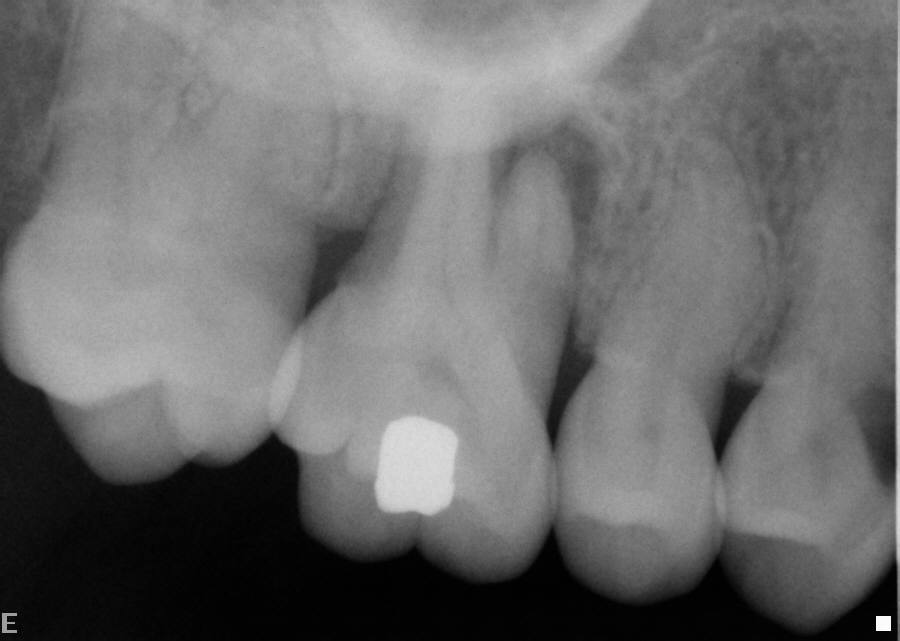

A large filling has killed the nerve in the tooth. Options are root treatment (endodontics) or extraction.

The tooth had an extremely curved root. After endodontics, the tooth does not need to be extracted and is functional.